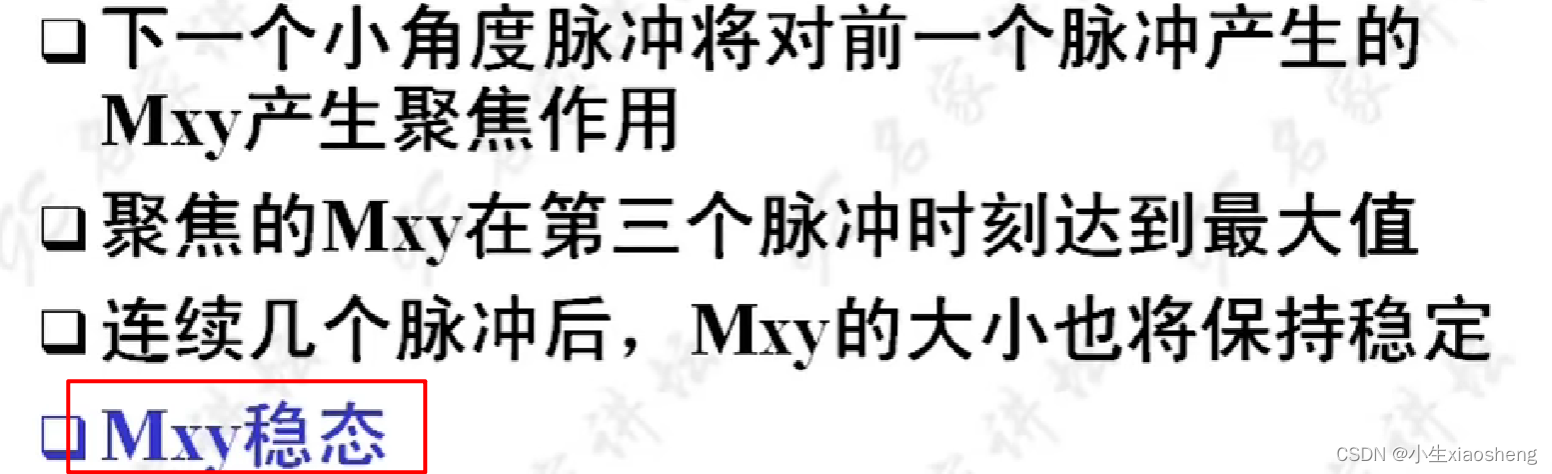

GRE序列中的稳态:流入的和流出的量是一样的,那么容器中的数据一直都是一样的。

第一次参数的横向脉冲没有全部恢复过来,当第二次脉冲过来时会存在聚焦使得整个脉冲变大,而这个变大的就是SSFP-REF指的是稳态自由进动(Steady-State Free Precession, SSFP)序列中的参考回波(Reference Echo),正常横向的脉冲就叫SSFP-FID。